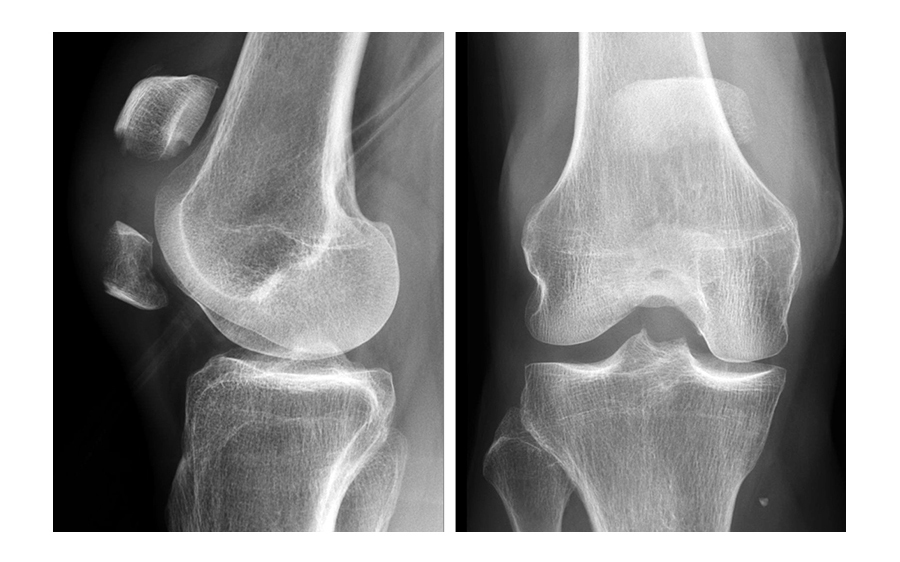

A 73-year-old woman sustained a right 34-C3.1 patella fracture during a hiking injury (Fig 1). X-ray analysis revealed that the distal pole was fractured in four fragments (Fig 2). After fracture reduction, a three-hole plate was used with three inferior to superior locking screws in the coronal plane through the holes of the plate legs and five anterior to posterior locking screws (Fig 3 and Fig 4).

A 71-year-old obese woman with osteoporosis sustained a fall from standing height with a direct blunt trauma on the left knee. It was impossible for her to walk or extend the knee. X-rays revealed a complex patella fracture with a comminuted distal pole (Fig 5).